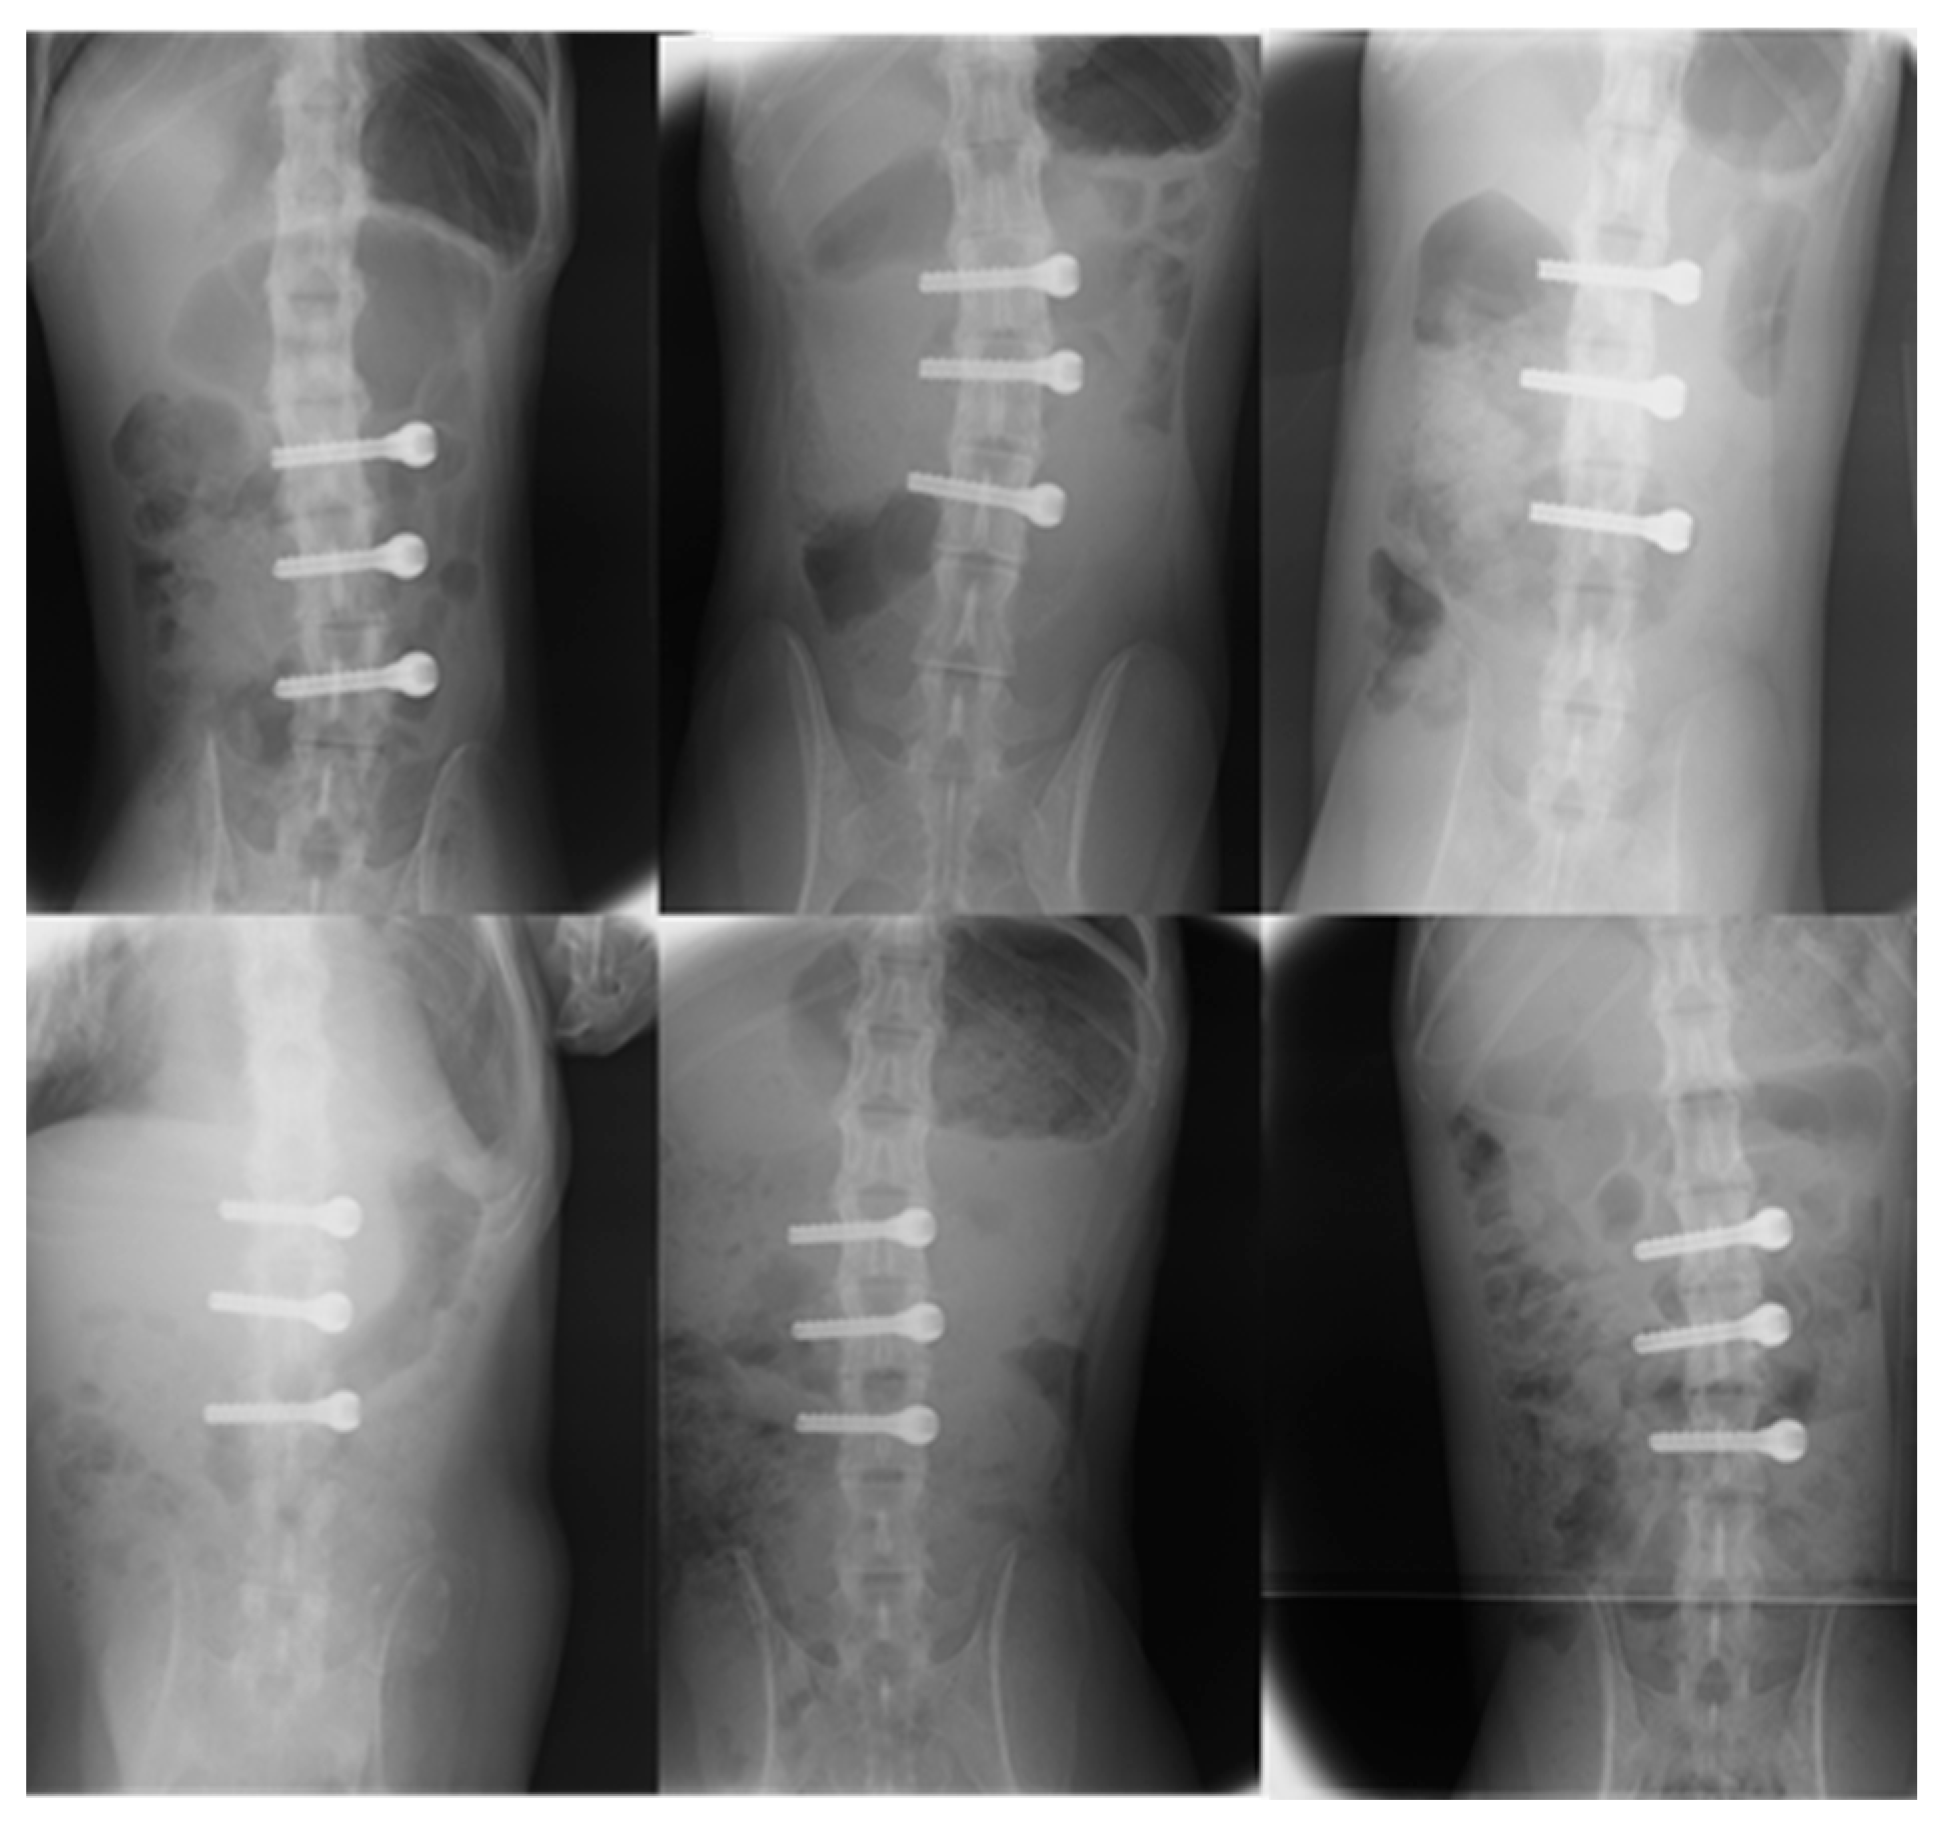

All animals were female, and there were no significant differences regarding age, blood test results, radiography and MRI of the lumbar spine, bone mineral density, or body weight (Table 2). All animals that underwent screw implantation—either uncoated or coated with FGF-CP composite layers—survived for 85 days and demonstrated transient weight loss. None exhibited weight loss exceeding 15%, which was the stopping criterion. In both groups, no blood tests were abnormal, and plain radiography revealed no transparent bone images or deviation around the implant (Figure 2).

Figure 2. Radiographs (anteroposterior and lateral views) of the lumber spine 12 weeks after surgery (fibroblast growth factor-2–calcium phosphate (FGF-CP) group above, the control below). No lucent areas were observed around the screws in either group.